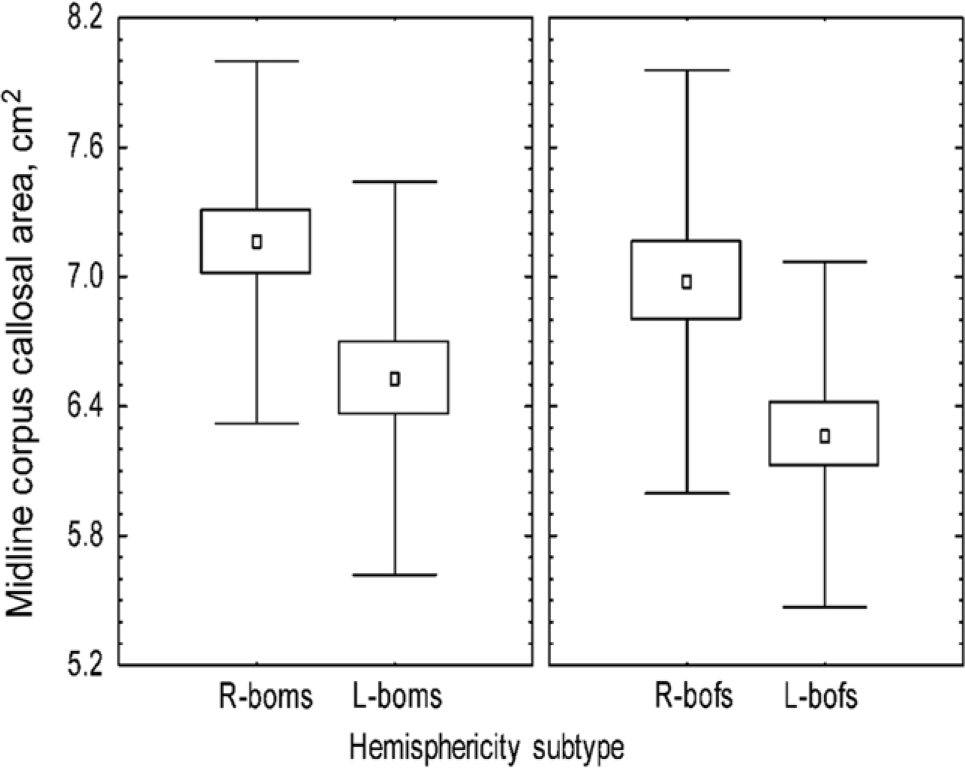

2.1.4 Hemisity and corpus callosum size

Individuals differ in the number of CC nerve fibers interconnecting

their cerebral hemispheres by about threefold. Using quantitative MRI, we found the midline CC area of 113 subjects was significantly correlated, not with handedness or sex, but with hemisity (Figures 1 and 2) (Morton, 2006). That is, right brain-oriented individuals of either sex had significantly larger CCs than left brain-oriented persons.

Figure 1. Effect of sex and hemisphericity upon corpus callosal area.

Figure 2. Hemisphericity vs. sex: size range of corpus callosal area.

2.1.8 RP hemisity dominance

Of the couples with opposite hemisities, the RP globally oriented partners were more dominant, and the LP detail-oriented partners were more supportive as shown in Table 5. This might be predicted from the observation that RPs are bold and outgoing, as compared to LPs who are more cautious and conservative. RPs also may be more cross-connected because their executive output often comes from the hemisphere opposite their language hemisphere. This may contribute to the observation that the medial CC area is considerably larger in RPs (Morton & Rafto, Reference Morton and Rafto2010).

5. In RPs, the CC was up to three times larger than in LPs.

3.2 Hemisity and corpus callosum size

It was found that those RPs with their final ACC executive output on the right side of the brain have significantly larger corpus callosi (Morton, 2006). This may be a consequence of their executive output module being on the opposite side of the brain from the commonly left hemisphere language module. Those LPs with their executive output on the same side as their language module would not be expected to need as much trans-hemisphere connectivity as RPs would. Thus, LPs would thus be expected to have smaller corpus callosi. Beyond this may be other factors that are related to the top-down, bottom-up specialization of the left and right cerebral hemispheres (Levy, Reference Levy1969; Sperry, Reference Sperry1982).